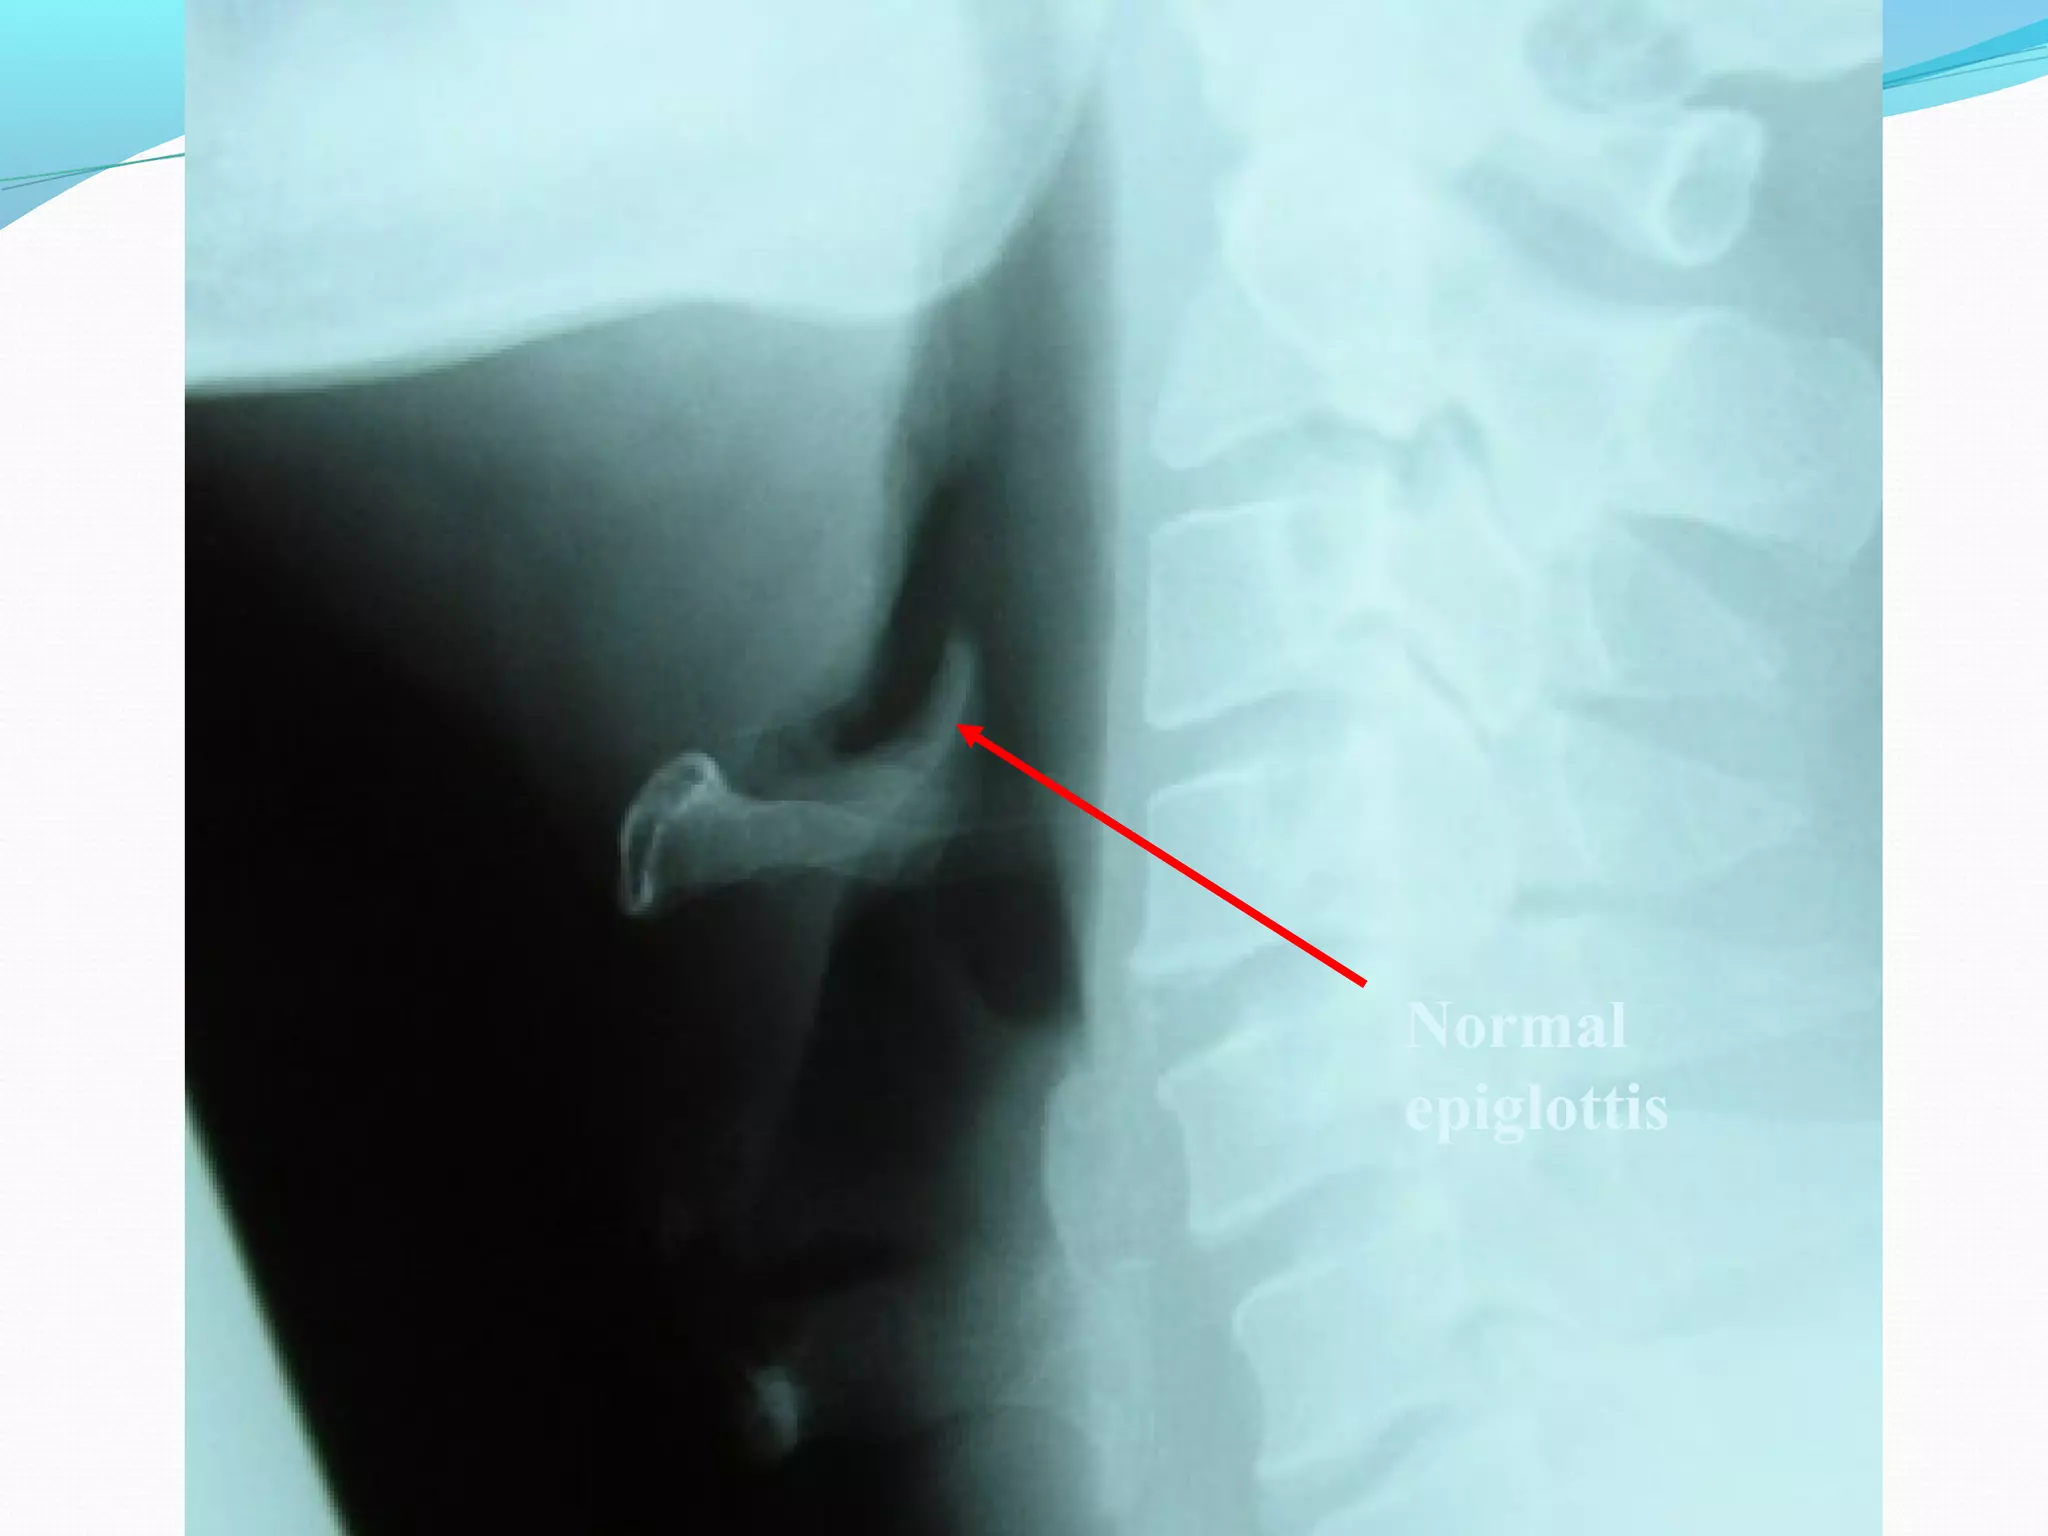

Epiglottitis

Indirect Laryngoscopy

Flexible Fiberoptic nasopharyngoscope

Lateral neck X-ray - thumb sign

Normal

epiglottis